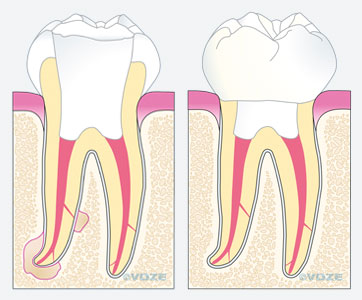

Haben sich an einem Zahn Bakterien im Sinne einer Karies angesiedelt, so besteht die Möglichkeit, dass der Zahnnerv infiziert wird (Bild Mitte). Als Folge dessen reagiert der Zahnnerv mit einer Entzündung, die zu einem Absterben des Nervens führen kann. Die Bakterien können sich dann im Wurzelkanalsystem innerhalb des abgestorbenen Nervgewebes vermehren und im Kieferknochen eine Entzündung hervorrufen. Diese Entzündung kann zu einer häufig zu beobachtenden Aufklopfempfindlichkeit des erkrankten Zahnes und einem Anschwellen der betroffenen Region führen. In seltenen Fällen können aber auch Unfälle oder zahnärztliche Behandlungen Ursache für die Erkrankung eines Zahnnervs sein.

Ziel dieser Maßnahmen ist es, das ursprüngliche Kanalsystem möglichst in einen keimarmen und sauberen Zustand zu bringen. Dieses hört sich zunächst sehr einfach an, doch bergen z. B. kleine Seitenkanäle die Gefahr einer möglichen Reinfektion (siehe Pfeile in Bild links und rechts). Auch diese müssen sorgfältig gereinigt und möglichst perfekt aufgefüllt werden. Aus diesem Grund nehmen wir uns für Ihren Zahn die entsprechende Zeit, um die oben beschriebene chemomechanische Desinfektion durchzuführen.

Nach vollständiger Instrumentation und Desinfektion des Wurzelkanalsystems muss das entstandene Hohlraumsystem mit einem Füllmaterial bakteriendicht versiegelt werden. Optimale Ergebnisse lassen sich mit der sogenannten dreidimensionalen thermoplastischen Obturation erreichen: Eine Art Gummi wird in erwärmten, fließfähigem Zustand in die Kanäle eingebracht und durch nachfolgender Kompression in die Hohlräume hineingepresst. Anschließend wird der Zahn mit einem stabilen Aufbau fest verschlossen (Bild links). Dieser dient auch als Vorbereitung für eine spätere eventuell notwendige Überkronung (Bild rechts). In den folgenden Monaten heilt die Entzündung um die Wurzelspitzen des jeweiligen Zahnes ab, der zuvor geschwundene Knochen regeneriert sich wieder (Fallbeispiel im nächsten Abschnitt)